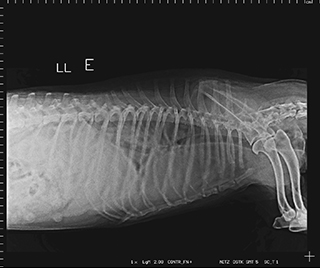

Radiologia Digital Direta / Digital Radiography

As radiografias geradas digitalmente podem ser transmitidas para iPad Apple®, notebooks e smartphones.

iPad com tela Retina Apple® possibilita a visualização das imagens com maior qualidade diagnóstica.